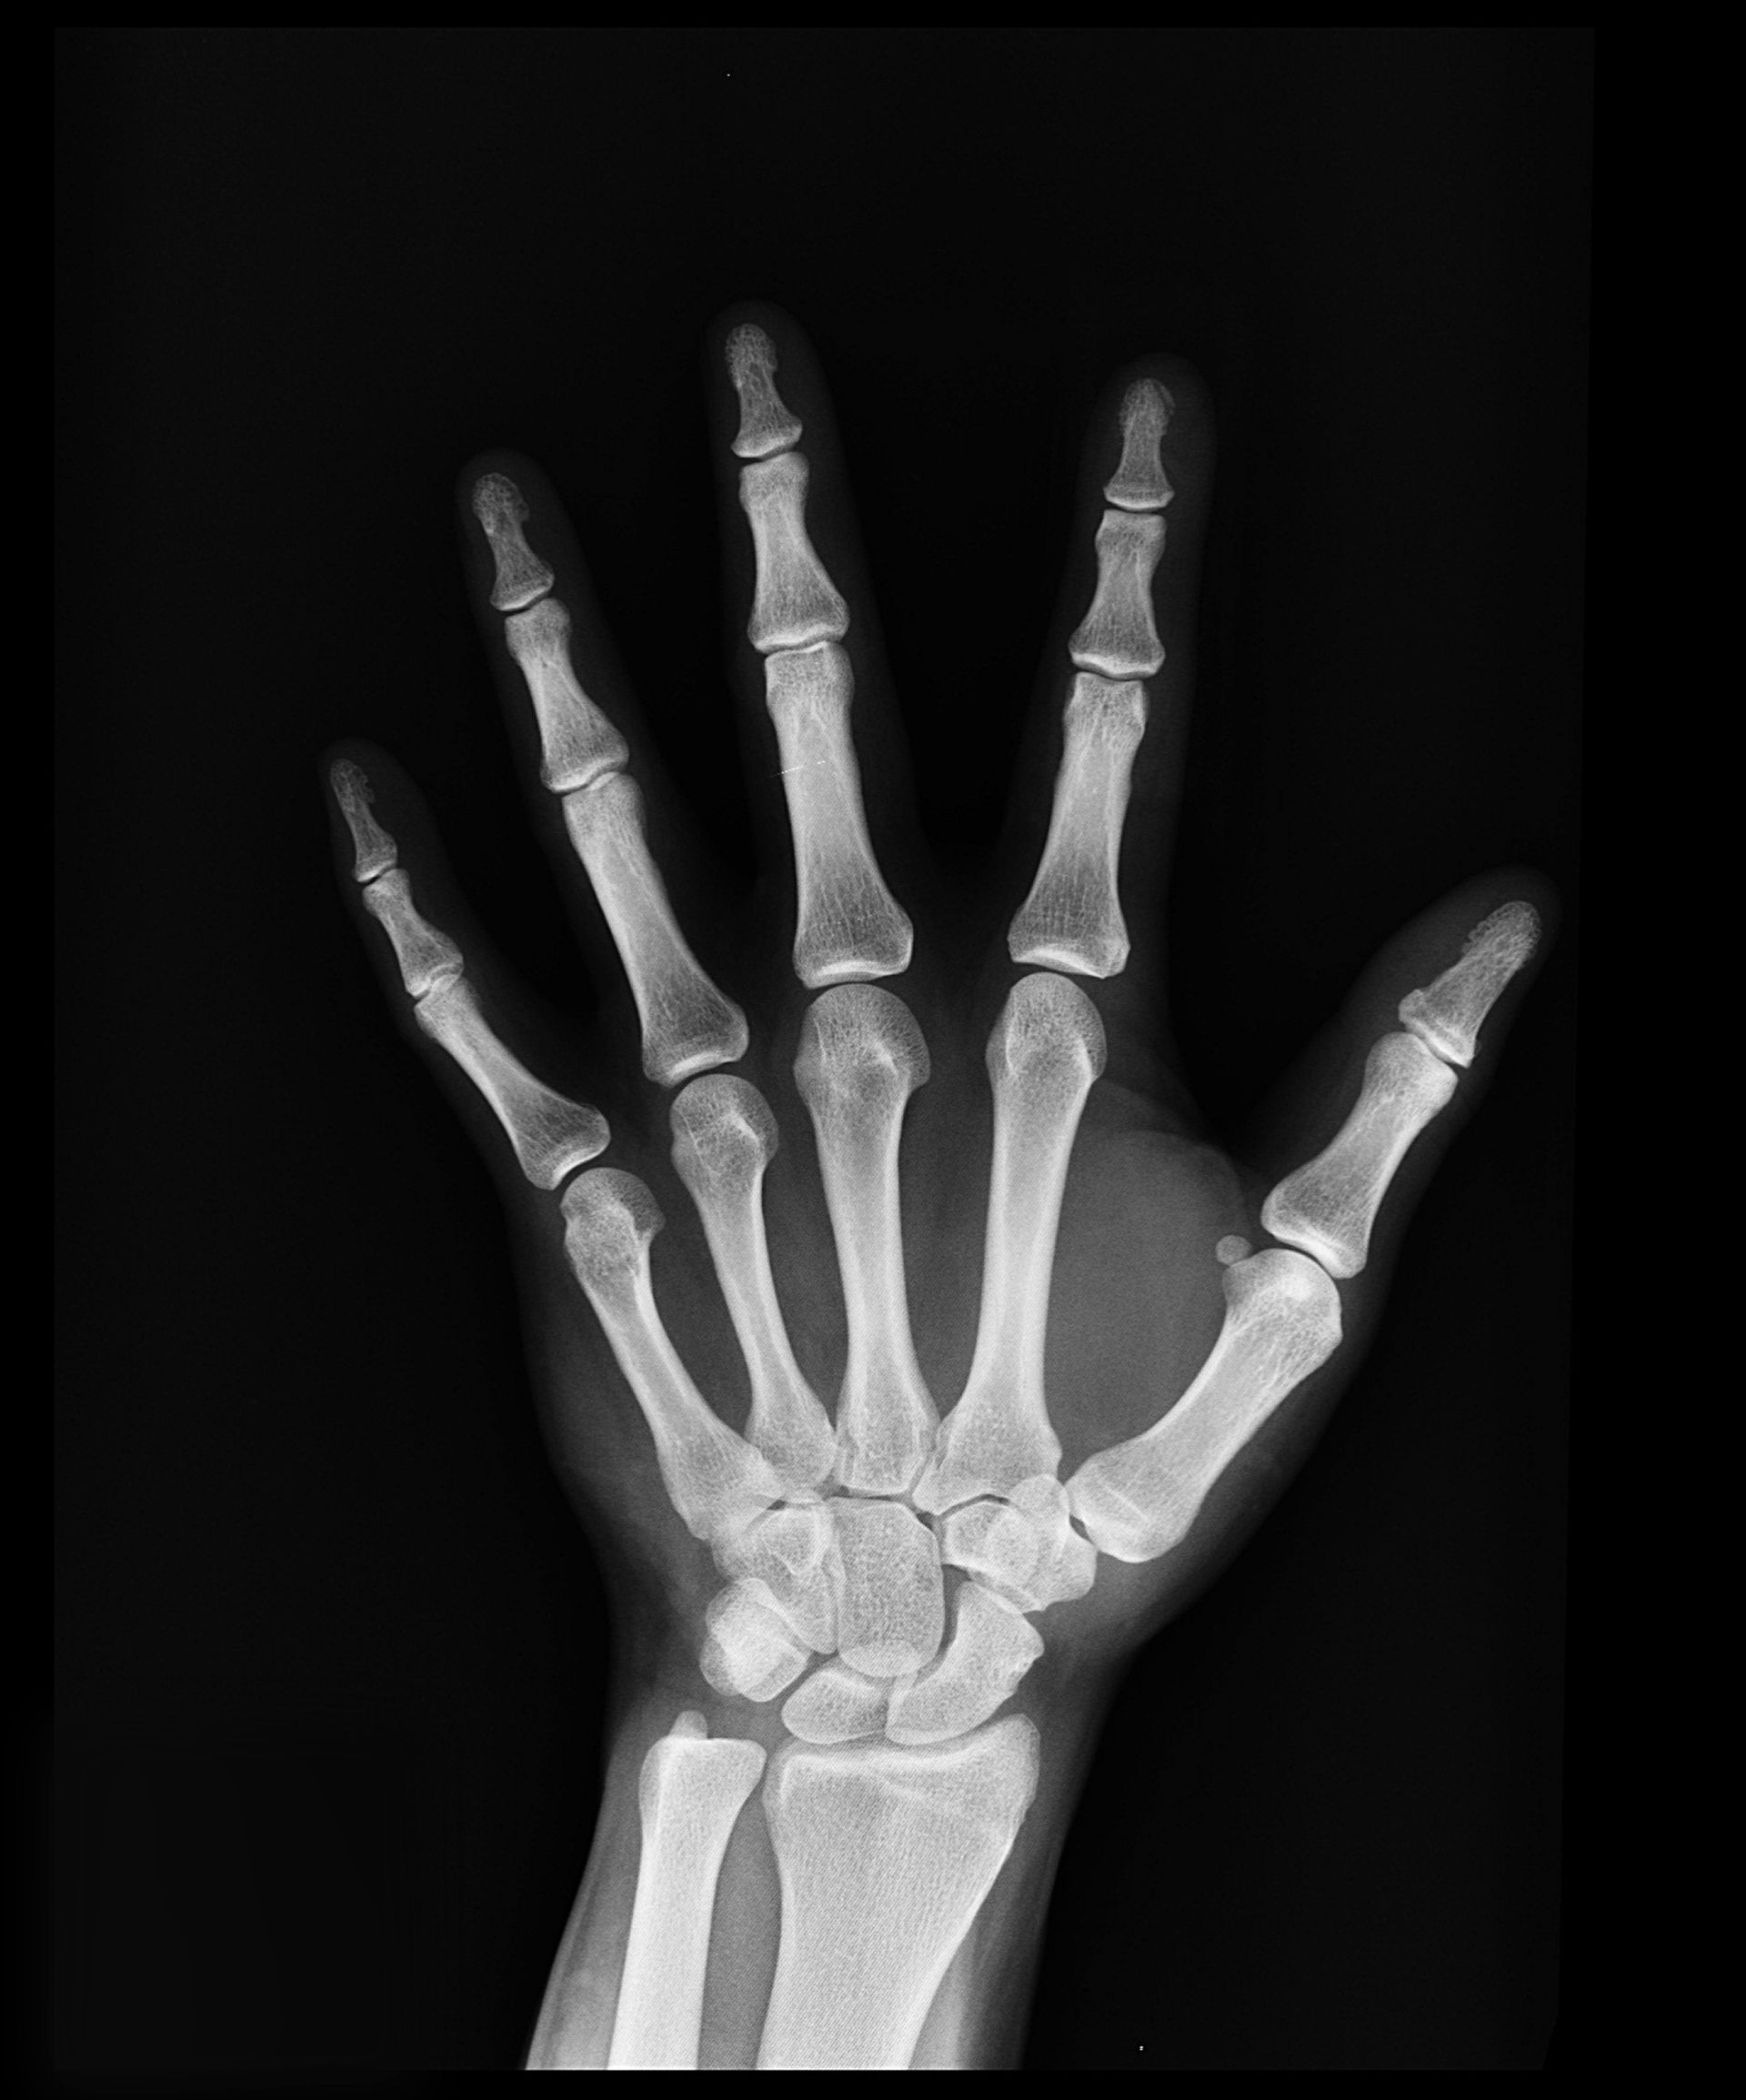

P1NP is a marker of bone turnover, and made during collagen synthesis. Collagen is a component of bone.